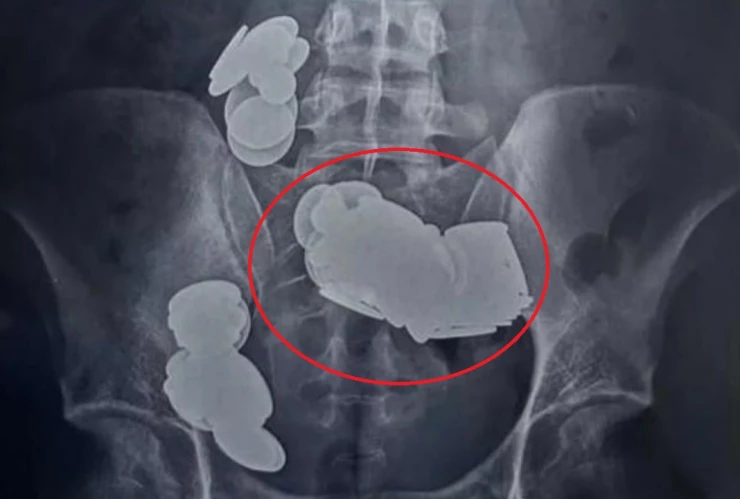

Fue a través de una radiografía de su abdomen, que se pudo observar que en el intestino resguardaba diversos objetos metálicos, y con una tomografía computarizada abdominal, se pudo detectar que tenía un número significativo de ellos obstruyendo sus intestinos, por lo que tuvo que ser llevado de urgencia para una cirugía.

Luego de algunas horas de intervención, el personal médico logró extraer 37 imanes de diversas formas, así como 39 monedas de uno, dos y cinco rupias.

Por si esto no fuera suficiente, durante la cirugía, se descubrió que el metal había formado dos bucles separados en el intestino delgado, provocando una atracción magnética que rompió los órganos internos; no obstante, estos objetos fueron retirados y se logró reconectar las zonas dañadas.